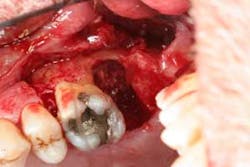

Figures 5a and 5b: Osseous surgery in the upper right quadrant with debridement of root surfaces and then regeneration.

Briefly, during osseous surgery, the upper right molars were treated with a combination of autograft and platelet-derived growth factor/Beta-tricalcium phosphate along with a porcine collagen graft (figures 5a and 5b). The upper left osseous surgery consisted of the same treatment (figures 6a and 6b), but also included the extraction of a hopeless tooth No. 15. Once again, the anterior osseous surgery consisted of the same regenerative materials as the former surgeries but with the addition of a porcine soft-tissue graft (figures 7a, 7b, and 7c). After the initial healing phase, the patient was placed on a strict home-care regimen and was seen every eight to 12 weeks for hygiene recare. The patient maintained excellent hygiene throughout the five-year follow-up period.